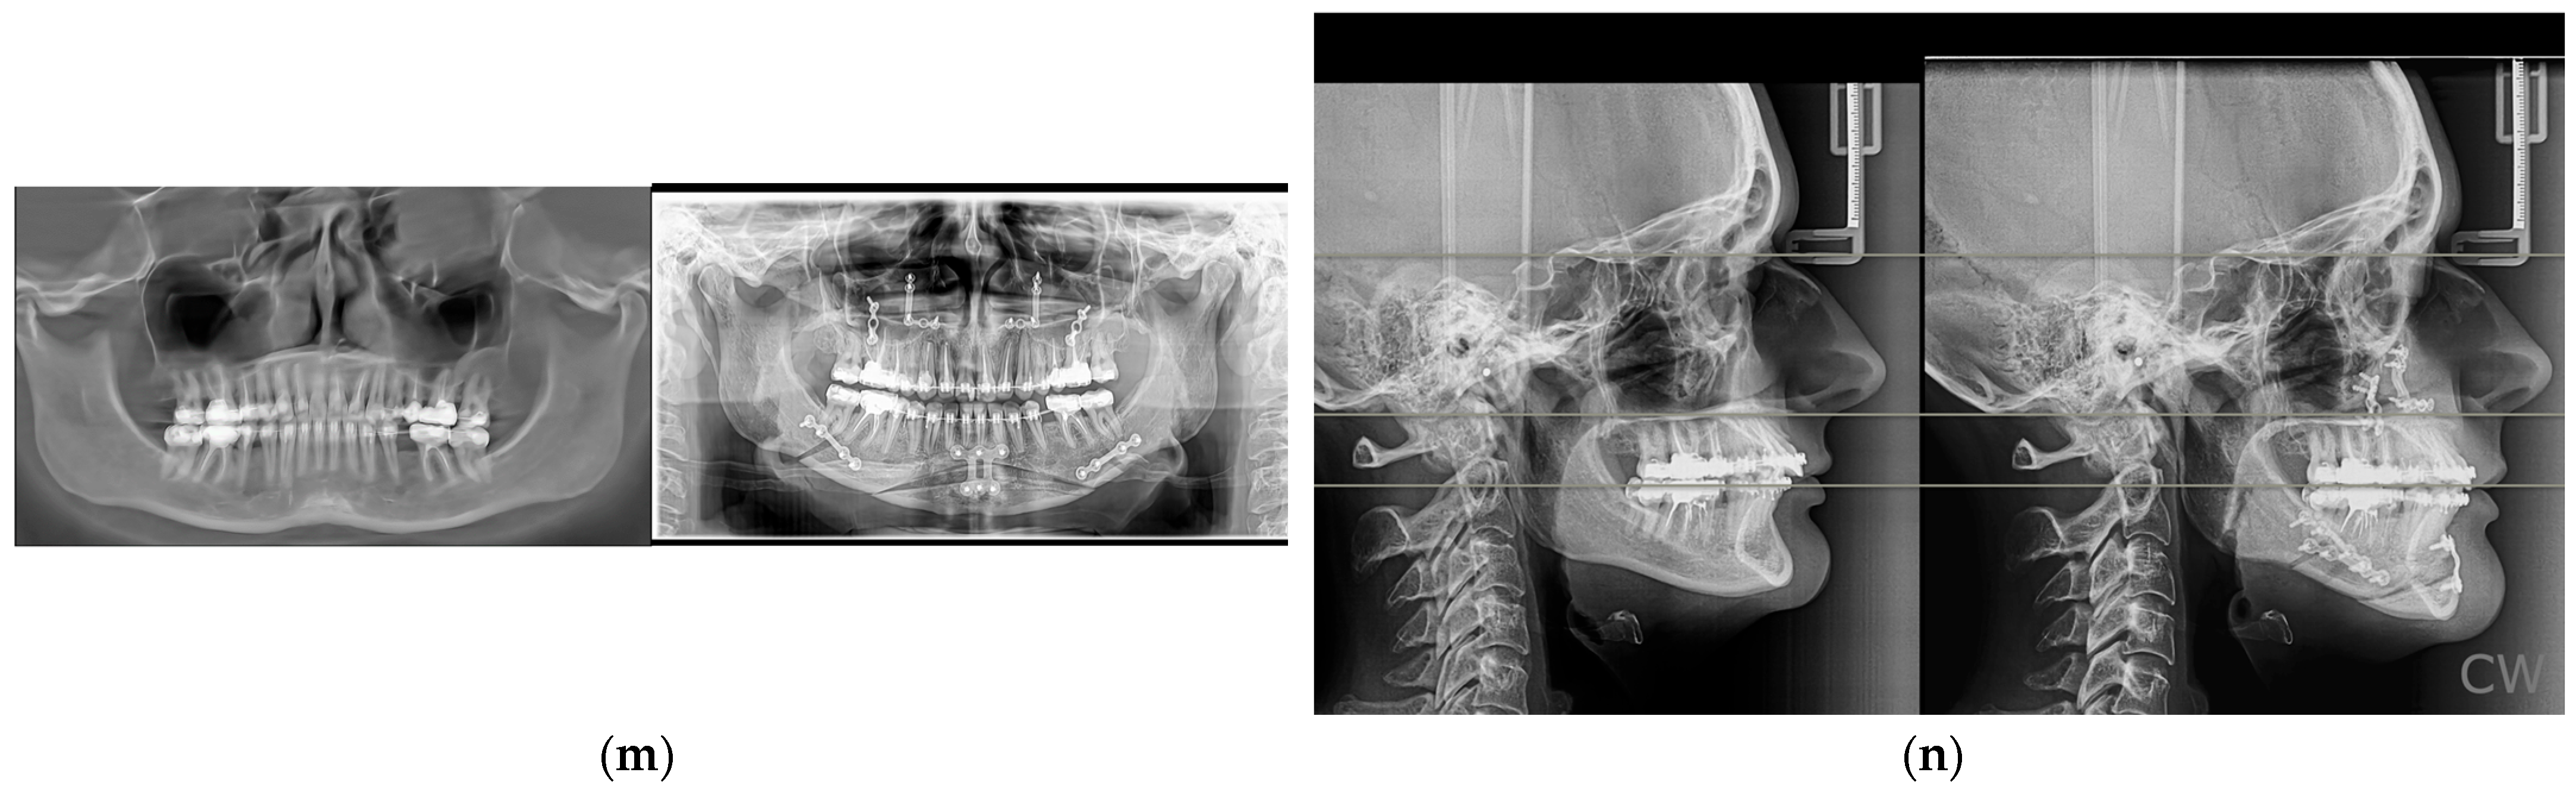

- Possessed complete diagnostic documentation, including CBCT scans, cephalometric radiographs, intraoral scans, and standardized clinical photographs;

- Specific radiographs depending on the case: panoramic radiograph (OPG), lateral and frontal cephalograms, and CBCT scans (large field of view).